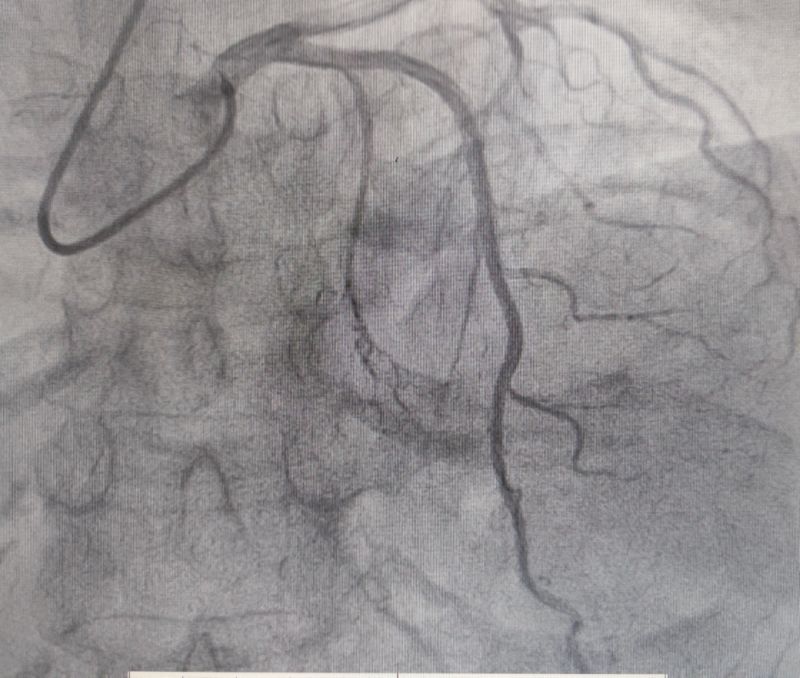

冠脈造影

經(jīng)過(guò)多輪嚴(yán)謹(jǐn)?shù)男g(shù)前討論,在吳棟梁院長(zhǎng)的專業(yè)指導(dǎo)下,崔旭輝主任醫(yī)師團(tuán)隊(duì)決定在臨時(shí)起搏器的安全保護(hù)下,為患者實(shí)施冠狀動(dòng)脈造影術(shù)及室間隔化學(xué)消融術(shù)。術(shù)中,團(tuán)隊(duì)通過(guò)造影精準(zhǔn)鎖定第一穿隔支為消融靶血管。測(cè)壓數(shù)據(jù)顯示:左室壓260/15mmHg,流出道173/6mmHg,主動(dòng)脈壓106/70 mmHg,壓力階差達(dá)87mmHg。隨后,團(tuán)隊(duì)使用2.0X15mm預(yù)擴(kuò)球囊以8atm壓力阻斷第一穿隔支遠(yuǎn)端血流1分鐘,再次測(cè)壓時(shí),壓力從269/7mmHg驟降至174/4mmHg,這一結(jié)果充分證實(shí)該血管正是室間隔的有效供血血管。緊接著,團(tuán)隊(duì)通過(guò)SPRINTER OTW2.0×8mm球囊緩慢注入1.4ml無(wú)水酒精。10分鐘后復(fù)測(cè),左心室壓降至136/5 mmHg,主動(dòng)脈壓為112/93 mmHg。術(shù)后第2天,王女士胸悶、氣短、心悸等不適癥狀完全消失。復(fù)查心臟彩超顯示:EF值與FS值保持穩(wěn)定,收縮期左室流出道血流速度降至252cm/s,PG值為25mmHg。